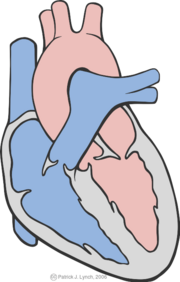

| 13:47, 25 September 2007 | PLAXLynch.png (file) |  |

64 KB | Vdbilt | Parasternal long axis view | 1 |